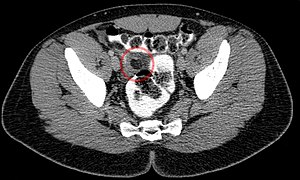

Epiploic appendagitis in computed tomography.

Epiploic appendagitis seen on CT scan.

Ultrasound and CT scans are the normal means of positive diagnosis of epiploic appendagitis. Ultrasound scans show "an oval, non-compressible hyperechoic mass with a subtle hypoechoic rim directly under the site of maximum tenderness".[5] Normally, epiploic appendages cannot be seen on CT scan.[5] After cross-sectional imaging and the increased use of abdominal CT for evaluating lower abdominal pain, EA is increasingly diagnosed. Pathognomonic CT scan data represent EA as 2–4 cm, oval shaped, fat density lesions, surrounded by inflammation. Contrasting with diverticulitis findings, the colonic wall is mostly unchanged.